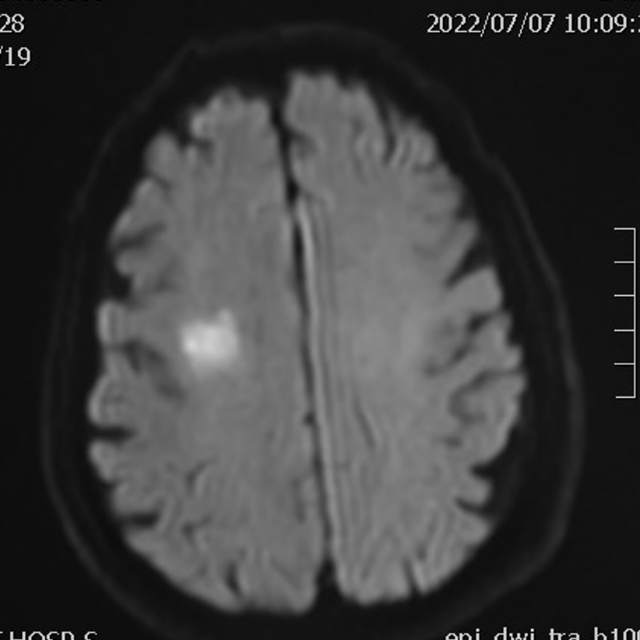

78岁老年男性,最近一个半月来已经和家里人没法正常交流,认知能力大幅下降,在农村,可能也就认为年龄大了,听天由命了。可老人家就是福大命大,有亲戚做医生,间隔17天先后为老人做了两次头颅MRI,发现脑梗塞,右侧血管长节段严重狭窄,右侧大脑半球缺血严重(图6,满江红),手术风险大……,家属经过反复咨询、犹豫、权衡,选择了保守治疗,毕竟老人年龄大了,手腿现在还能动,手术也有风险,时机也不是太好,国外研究不推荐,国内研究也不支持,保守治疗似乎是个不错的选择。然而,保守期间,患者反复出现脑梗塞,认知能力进行性下降,最终促使家属决定采用外科干预。然而,对医生而言,在梗塞的急性期处理这种长节段密布分支血管的病变风险不言而喻,而一味的观望和等候肯定不是最佳选择。过一点,可能出血;欠一点,可能闭塞。全面认真评估后,我们顺利为老人家完成了I期治疗,老人家的“火焰山”(图6)变成了“绿油油”充满生机的田野(图14),缺血明显改善,认知能力大幅提高,术后就能和家人正常交流了,也记起了很多以前忘记的事情……,家人很开心。